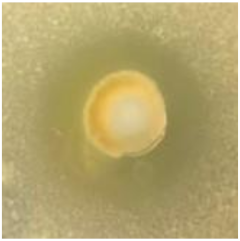

| AgNPs | 11.5 ± 1.7![]() | 10.6 ± 0.6![]() | 8.8 ± 0.5![]() | 8.8 ± 3.0![]() |

| Vancomycin | 22.5 ± 0.5![]() | 22.5 ± 0.5![]() | 8.0 ± 0.1![]() | 8.0 ± 0.2![]() |

| LL37 | 6.5 ± 0.1![]() | 6.5 ± 0.5![]() | 6.3 ± 0.1![]() | 6.2 ± 0.1![]() |

| Pexiganan | 9.0 ± 0.5![]() | 12.2 ± 0.6![]() | 8.0 ± 1.5![]() | 12.0 ± 0.1![]() |

| TTO | 20.2 ± 0.1![]() | 15.0 ± 0.5![]() | 15.5 ± 0.5![]() | 13.3 ± 0.3![]() |

| CLO | 21.5 ± 0.5![]() | 15.0 ± 1.0![]() | 15.0 ± 1.9![]() | 15.0 ± 0.6![]() |

| NO | 14.7 ± 0.4![]() | 10.0 ± 0.5![]() | 11.5 ± 0.5![]() | 6.8 ± 0.5![]() |